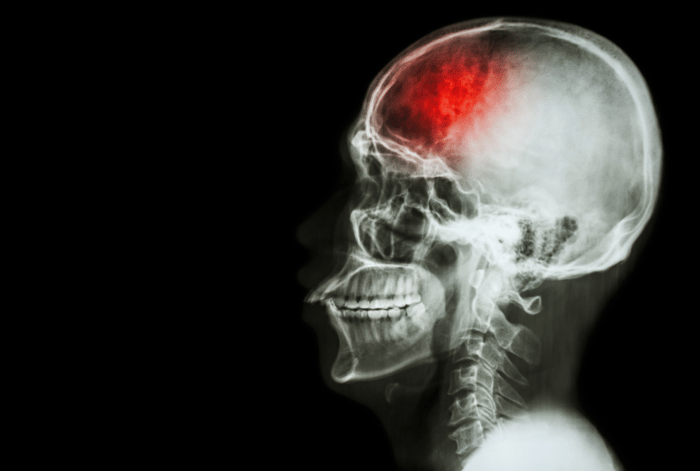

ก่อนที่จะพูดถึงเทป Kinesio เราก็ต้องพูดถึงโรคหลอดเลือดสมองกันก่อน โรคหลอดเลือดสมองเป็นพยาธิสภาพที่พบได้ค่อนข้างบ่อยในปัจจุบัน อาจเป็นเพราะอาหารที่รับประทาน พฤติกรรมการใช้ชีวิต ฯลฯ แต่เมื่อเกิดพยาธิสภาพขึ้นไม่ว่าเกิดจากหลอดเลือดสมองตีบ (อุดตัน) หรือหลอดเลือดสมองแตก จะส่งผลให้เกิดความผิดปกติต่อร่างกาย อาทิเช่น มีอาการชาและ/หรืออ่อนแรงครึ่งซีกของร่างกาย พูดลำบาก ทรงตัวและเคลื่อนไหวร่างกายลำบาก ฯลฯ โดยทั่วไปการรักษาทางกายภาพบำบัดจะเริ่มทันทีที่อาการของผู้ป่วยเริ่มคงที่ ในช่วงแรกของอาการผู้ป่วยจะมีการอ่อนแรง (Flaccid) และต่อมาจะเกิดอาการเกร็งตัวของกล้ามเนื้อที่เรียกว่าภาวะ Spasticity ตามขึ้นมาและร่วมกับอาการผิดปกติอื่น ๆ